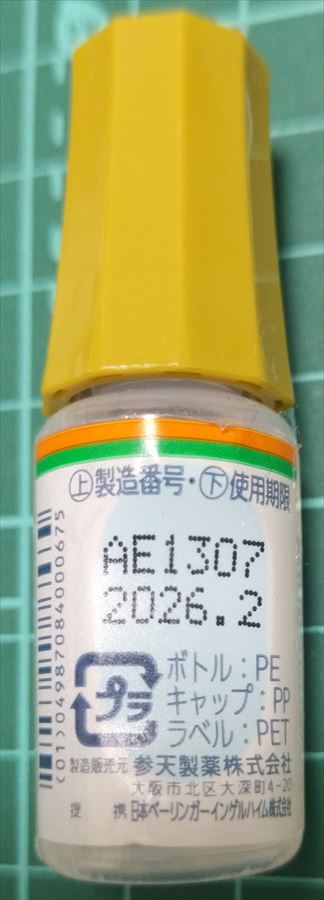

2024.3.9 鼻炎と目のかゆみがひどく、オロパタジン⇒デザレックス&点眼薬 アレジオン に変更 2.10 血液検査結果